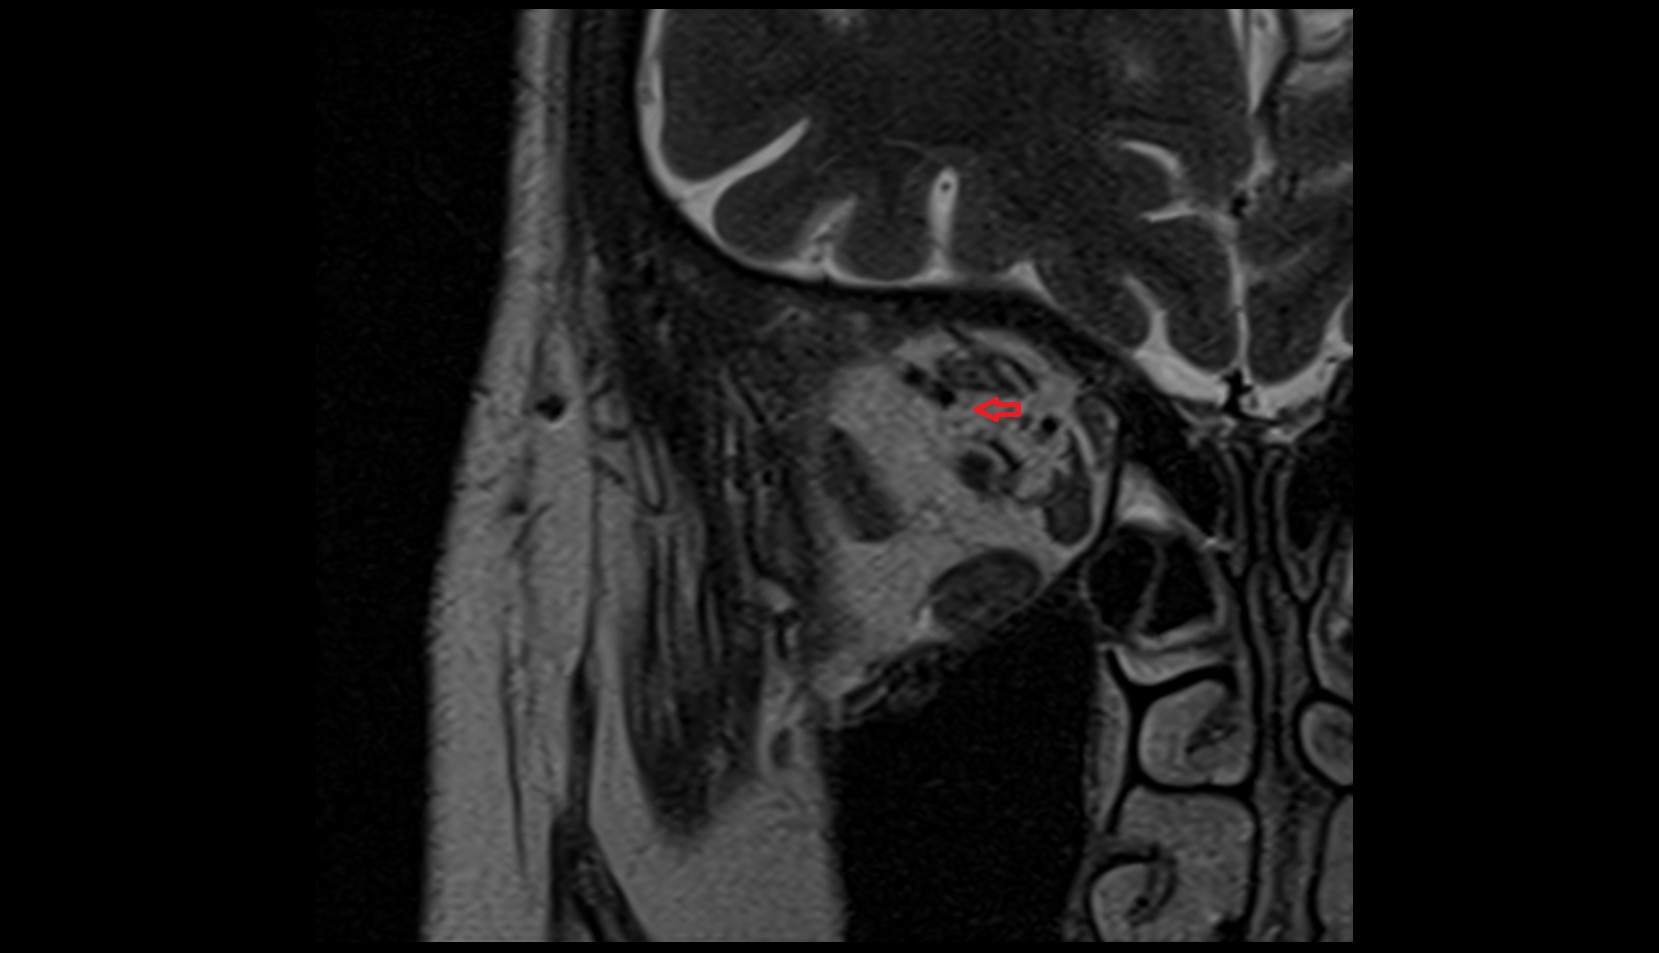

- Placenta

- Uterus (pregnancy)

- Amniotic fluid

- Umbilical cord

- Fetal brain

- Fetal cerebellum